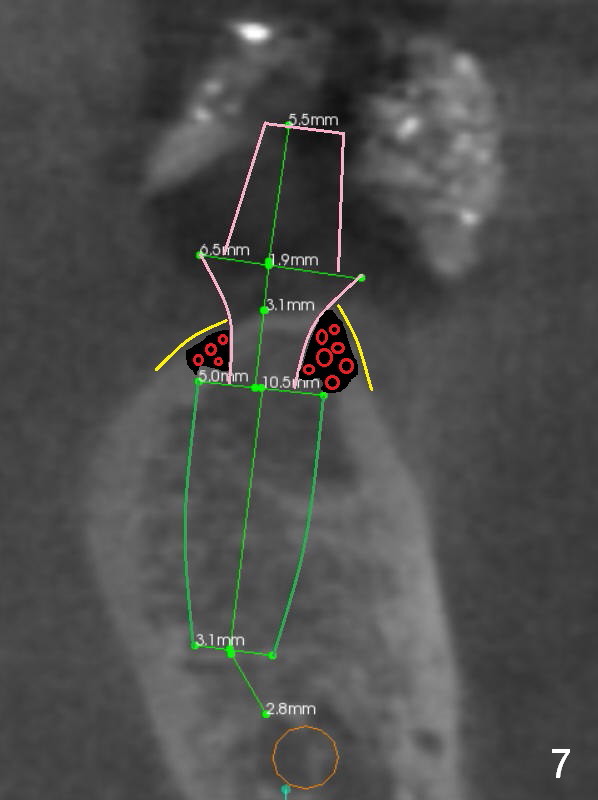

Pointed Ridge at #19

A 56-year-old man decides to have an implant at #19 after those at #13 and 14 (Fig.1 (S: CT stent)). The coronal section shows the pointed ridge (Fig.2 *). For easy implant placement and reduction in thread exposure, the ridge will be trimmed flat (Fig.3 (black area), or more exactly (funnel shaped Fig.4 (arrowheads to accommodate the shape of the cemented abutment (pink)) or concave (Fig.6)). After placing a 5x10 mm UF implant (green), bone graft to be placed (Fig.5,7 red circles) remains in place followed by collagen dressing (Fig.7 yellow lines).

Since the bone density is low (100-400 U), the last drill will be one for a 4.5 mm implant (underprep). To save the autogenous bone, reduce drill speed to 50 RPM when starting using the drill for 3.8 mm implant.